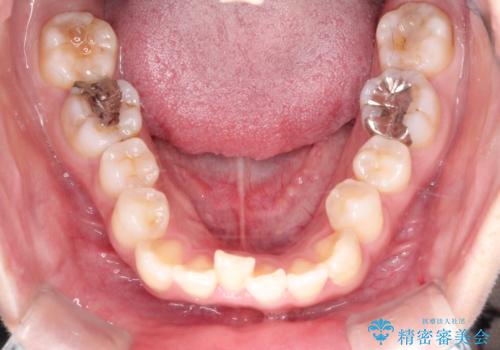

- 主訴:口元を下げて前突感を無くしたい、下の歯の凹凸も無くしたい

右側第二小臼歯、左側第一小臼歯、下顎両側第一小臼歯を抜歯しワイヤ-矯正を行いました。

骨格的顎の変位を認めたため、顔貌に対しピッタリ上下の歯の正中を合わせることは難しいと説明し、上下左右計4本小臼歯を抜歯しワイヤー矯正治療を行いました。